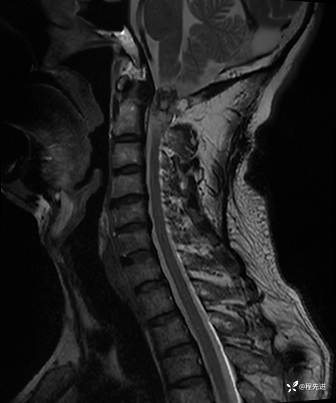

MRI平扫+增强:

T2压脂: